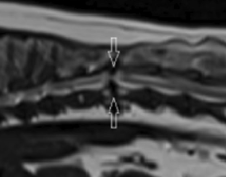

이 논문에서는 협착성 척추병증 즉, constrictive myelopathy라는 질환이 새롭게 퍼그에서 조명되고 있어 이를 소개하고 특성들에 대해서 나타내고 있다.